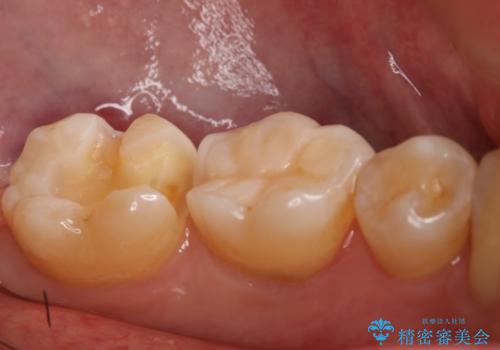

- 左下7番のCR劣化を自費治療にて希望された患者様です。

切削量を考慮してセラミックインレーでの治療を選択しました。

CR直下と隣接面にう蝕が進行していたので、除去した上で形成、印象しています。